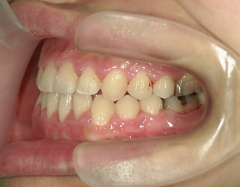

矯正歯科 治療前矯正歯科 治療前

主訴:受け口(反対咬合)を治したい

矯正歯科 治療前 急速拡大装置で上顎を広げた後、ワイヤーへ移行 非抜歯

no.31_7964_治療前_右 .JPGno.31_7964_治療前_正面 .JPGno.31_7964_治療前_左 .JPG